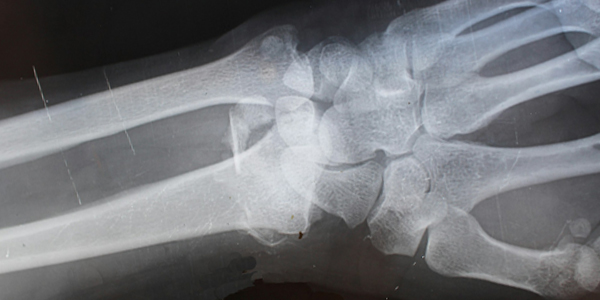

L’autopsie virtuelle est un outil radiologique permettant l’imagerie en coupes, via des scanners et IRM, afin d’avoir une documentation d’un corps et de ses éventuelles lésions. L’acquisition de ces images peut également se faire avec un produit de contraste injecté, rendant davantage visibles les vaisseaux sanguins du défunt.

Pionnier français de cette nouvelle pratique qui a émergé en 2002, Fabrice Dédouit détaille que les intérêts sont nombreux. Parmi eux, la conservation des images qui peuvent être interprétées autant de fois que voulu, « là où une autopsie médicolégale ne peut être réalisée qu’une seule fois. » Ces clichés ainsi produits sont d’autant plus utiles qu’ils concernent le corps entier. « Or, une autopsie traditionnelle ne permet pas d’arriver à ce niveau d’exhaustivité. Le scanner permet une visualisation parfaite des épanchements gazeux et des structures osseuses, pas forcément toutes faciles d’accès en pratique. »

Pour le médecin légiste, « ce qui est vraiment révolutionnaire, c’est l’injection du produit de contraste dans un corps défunt qui permet une précision inouïe. » Les chiffres sont clairs : en moyenne, une virtopsie avec cette injection diagnostiquera 40% de lésions supplémentaires qu’une autopsie classique, contre 15% sans injection. En plus d’être assez rapide, l’autopsie virtuelle produit des images de corps qui sont plus supportables pour la famille de la personne décédée et les jurés, et très utiles dans les procédures judiciaires.